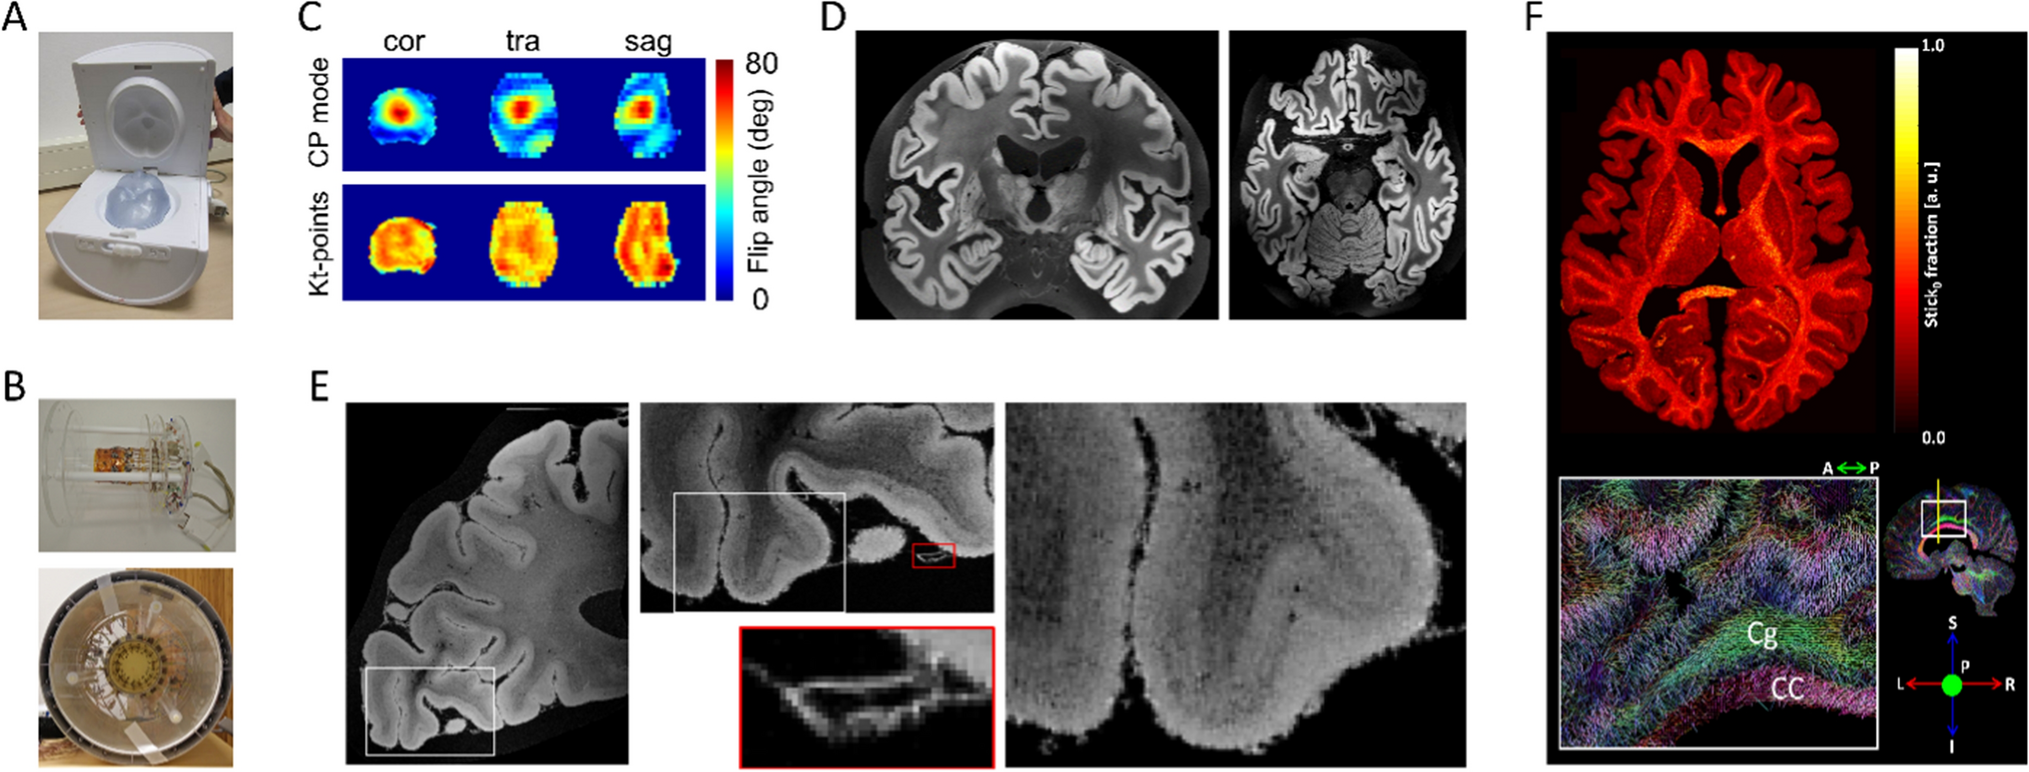

Small post-mortem human brain tissue samples can be used on pre-clinical MRI systems (animal scanners or spectroscopy systems) to examine and investigate fundamental neuroanatomy questions at the mesoscale [7679]. However, small bore scanners are limited to small tissue samples, for example on the order of millimeters. From about 2015 onward, the computational brain connectivity lab at Maastricht University undertook a program of RF coil construction and MR method development to investigate the limits of contrast and resolution on the 9.4 T large bore system for much larger human brain samples. The focus was on gradient-echo and diffusion imaging of post-mortem whole human brains and intact post-mortem human occipital lobes. Previous work had already shown that resolutions considerably superior to that achievable in vivo are attainable at 3 T and 7 T [8082]. Limiting factors in optimizing acquisitions further and using the advantages of 9.4 T were as follows: limited large-bore gradient performance, non-optimized RF coils for the intended samples, and RF field inhomogeneity over the brain at 9.4 T considerably higher than at 3 T or 7 T. For the RF coils, we set out to design and build several special purpose postmortem tissue coils, prominent among which are a 9.4 T 8-channel parallel transmit (pTx), 24-channel receive RF coil for whole post-mortem human brains (Fig. 7A) and a 16-channel cylindrical RF coil to image medium post-mortem occipital lobe samples (~ 80 × 80 × 80 mm3, Fig. 7B, [83]).

Fig. 7

A The custom-built 8Tx/24Rx 9.4 T whole post-mortem human brain RF-coil. B The custom-built 16Rx 9.4 T medium-sized post-mortem sample RF-coil outside of (top) and inside (bottom) the 16Tx ring C) B1+ maps showing transmit efficiency and homogeneity over the whole post-mortem brain with substantial inhomogeneity in standard circularly polarized (CP) mode, which is improved greatly with kT-points transmit phases optimized for homogeneity. D A coronal (left) and transverse slice (right) through early whole post-mortem brain 3D GE acquisitions at 200 µm isotropic. E Transverse slices through a GE acquisition at 60 μm isotropic of an occipital lobe sample in the medium-sample coil at different zoom levels. F kT-dSTEAM 400 μm diffusion results: a transverse slice through the Stick0 fraction map resulting from a Ball&Stick model fit (top) and direction color coded DTI primary eigenvector in a sagittal slice with zoom-in (bottom) CC corpus callosum, Cg cingulum

Mitigating the severe transmit (B1+) field inhomogeneity over the entire brain samples at 9.4 T could be dealt by using kt-points composite excitation pulses (Fig. 7C; [37, 44] and modifying kt-point refocusing pulses for use in diffusion weighted STEAM imaging [84]. Using these techniques, early 3D GE acquisition results quickly provided anatomical whole brain images at 200 µm isotropic and better (Fig. 7D; [85, 86]). For occipital lobe imaging 3D GE acquisition results could be brought beyond 100 µm isotropic up to 60 µm isotropic (Fig. 7E) with quantitative T2* and T2*-weighted contrast providing cortical layer specific details, such as the stripe of Gennari ([83] for further results and details).

For diffusion MRI (dMRI) in particular, restricted large-bore gradient performance is a limiting factor in combination with the decreasing T2 with increasing B0 as well as further decreases in water’s apparent diffusion coefficient (ADC) and T2 in fixed tissue [87]. The applied solutions were modifying kT-point pulses for use in diffusion-weighted STEAM imaging, creating kT-dSTEAM [84], achieving B1+ homogenization across whole human brain specimens and smaller sections and using the increased T1 with increasing B0 to compensate for decreasing T2 in diffusion weighting. Using kT-dSTEAM, ultra-high isotropic resolution data (400 μm, Figure F) at moderate b-values (3000 s/mm2) [84] and a high resolution (1000 μm) whole brain data at high b-value (6000–8000 s/mm2) could be obtained [84].